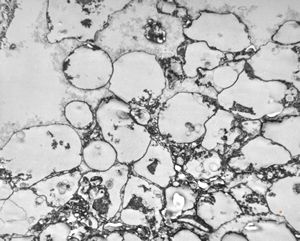

M,50y. | Pneumocystis carinii